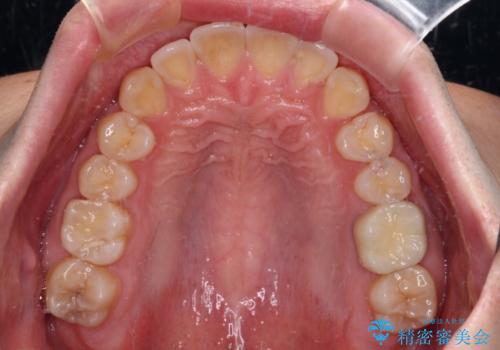

下顎前歯が思っていた以上に動きが悪く、想定よりも期間がかかってしまいました。

矯正治療後には気になっていた銀歯をセラミックで自然な色に仕上げました。